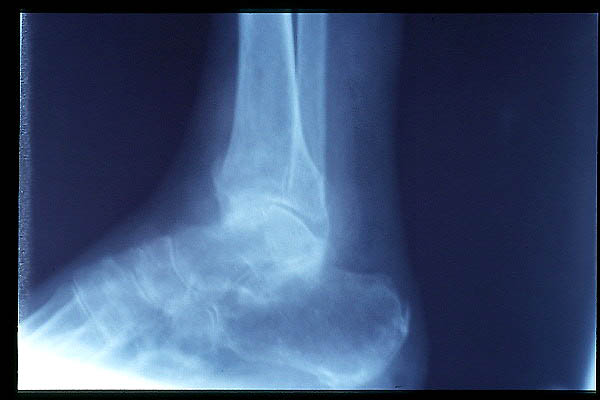

ACT Osteonecrosis de la cúpula astragalina por afectación vascular.